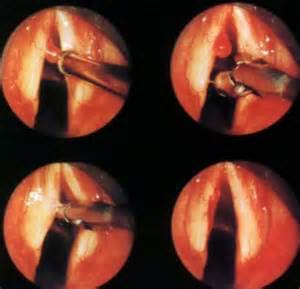

圖:聲帶息肉的內窺鏡檢查

2、一側或兩側聲帶邊緣有球狀或香腸狀的水腫樣增生物,聲門閉合不全。

聲帶息肉有時候會懸于聲門下,只有在呼吸的時候才能夠明顯的觀察到。經過喉鏡檢查,局限性聲帶息肉多在一側聲帶的前1/3部,基底小而有蒂,半透明淺灰色或淡紅色,圓形或橢圓形。自聲帶邊緣長出,可隨呼吸上下活動。彌漫型可見基底寬廣的半透明淡灰色或淡紅色腫塊,常發(fā)于一側,兩側均有者少見。

4、檢查見聲帶邊緣有灰白色水腫狀贅生物,多發(fā)生于聲帶前中1/3交界處,呈帶蒂狀。也有呈球形外觀或為廣基者。甚者聲帶全長水腫明顯,形如臥蠶狀,且可雙側同時患病。有些息肉可呈鮮紅色或暗紫色。聲帶的帶蒂息肉或球形息肉多為單側性。